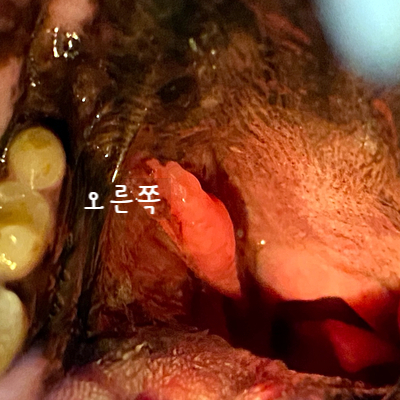

내시경 검사로 후두부를 확인했어요. 눈으로 확인하기 어려운 작은 변화도 내시경 검사를 통해 자세히 조사할 수 있었습니다.

후두부를 검사할 때는 연골의 크기 차이밖에 문제가 되지 않았습니다. 그래서 후두부에서 구강을 향해 천천히 내시경을 채취하면서 검사를 해 보았습니다.

◆ 편도선염과 부종

양쪽 편도선이 부어있는 것 같았어요 특히 왼쪽 편도선은 출혈까지 확인되었는데